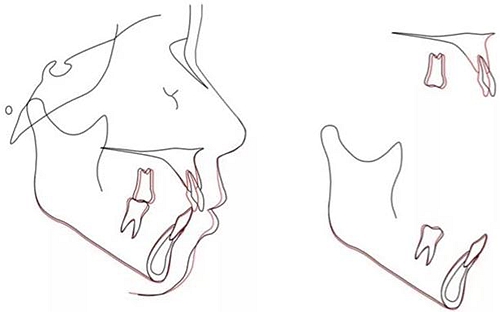

頭側(cè)分析提示為骨性安氏II類(ANB,8.4°;Wits,3.6mm),高角(SN-MP,44.9°),上頜切牙略舌傾(U1-SN,96.2°),下頜切牙略舌傾(IMPA,88。3°)(圖2;表)